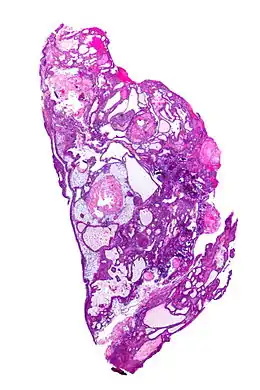

Le craniopharyngiome est une malformation tissulaire embryonnaire (c'est-à-dire apparue avant la naissance) de la région hypophysaire. Les raisons de cette malformation sont encore inconnues. La tumeur, souvent kystique, est visible à l'IRM (imagerie par résonance magnétique) et de nature bénigne. Elle se développe à partir des restes de la poche de Rathke, dans et au-dessus de l'hypophyse. Le craniopharyngiome se situe à proximité directe de zones du cerveau très importantes pour le développement somatique et psychique. La proximité du nerf optique peut aboutir à une réduction du champ visuel, voire une cécité.